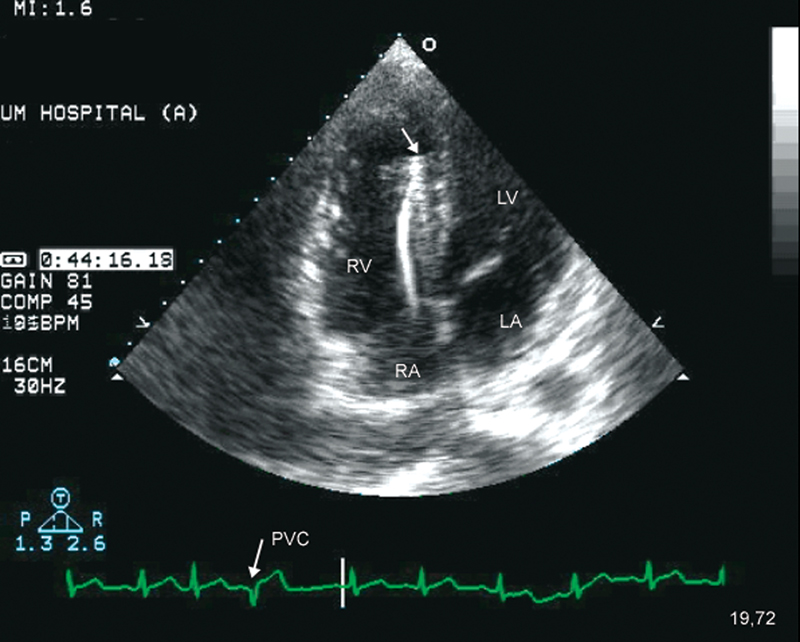

فحوصات تشخيصية لبعض امراض القلب والشرايين التاجية